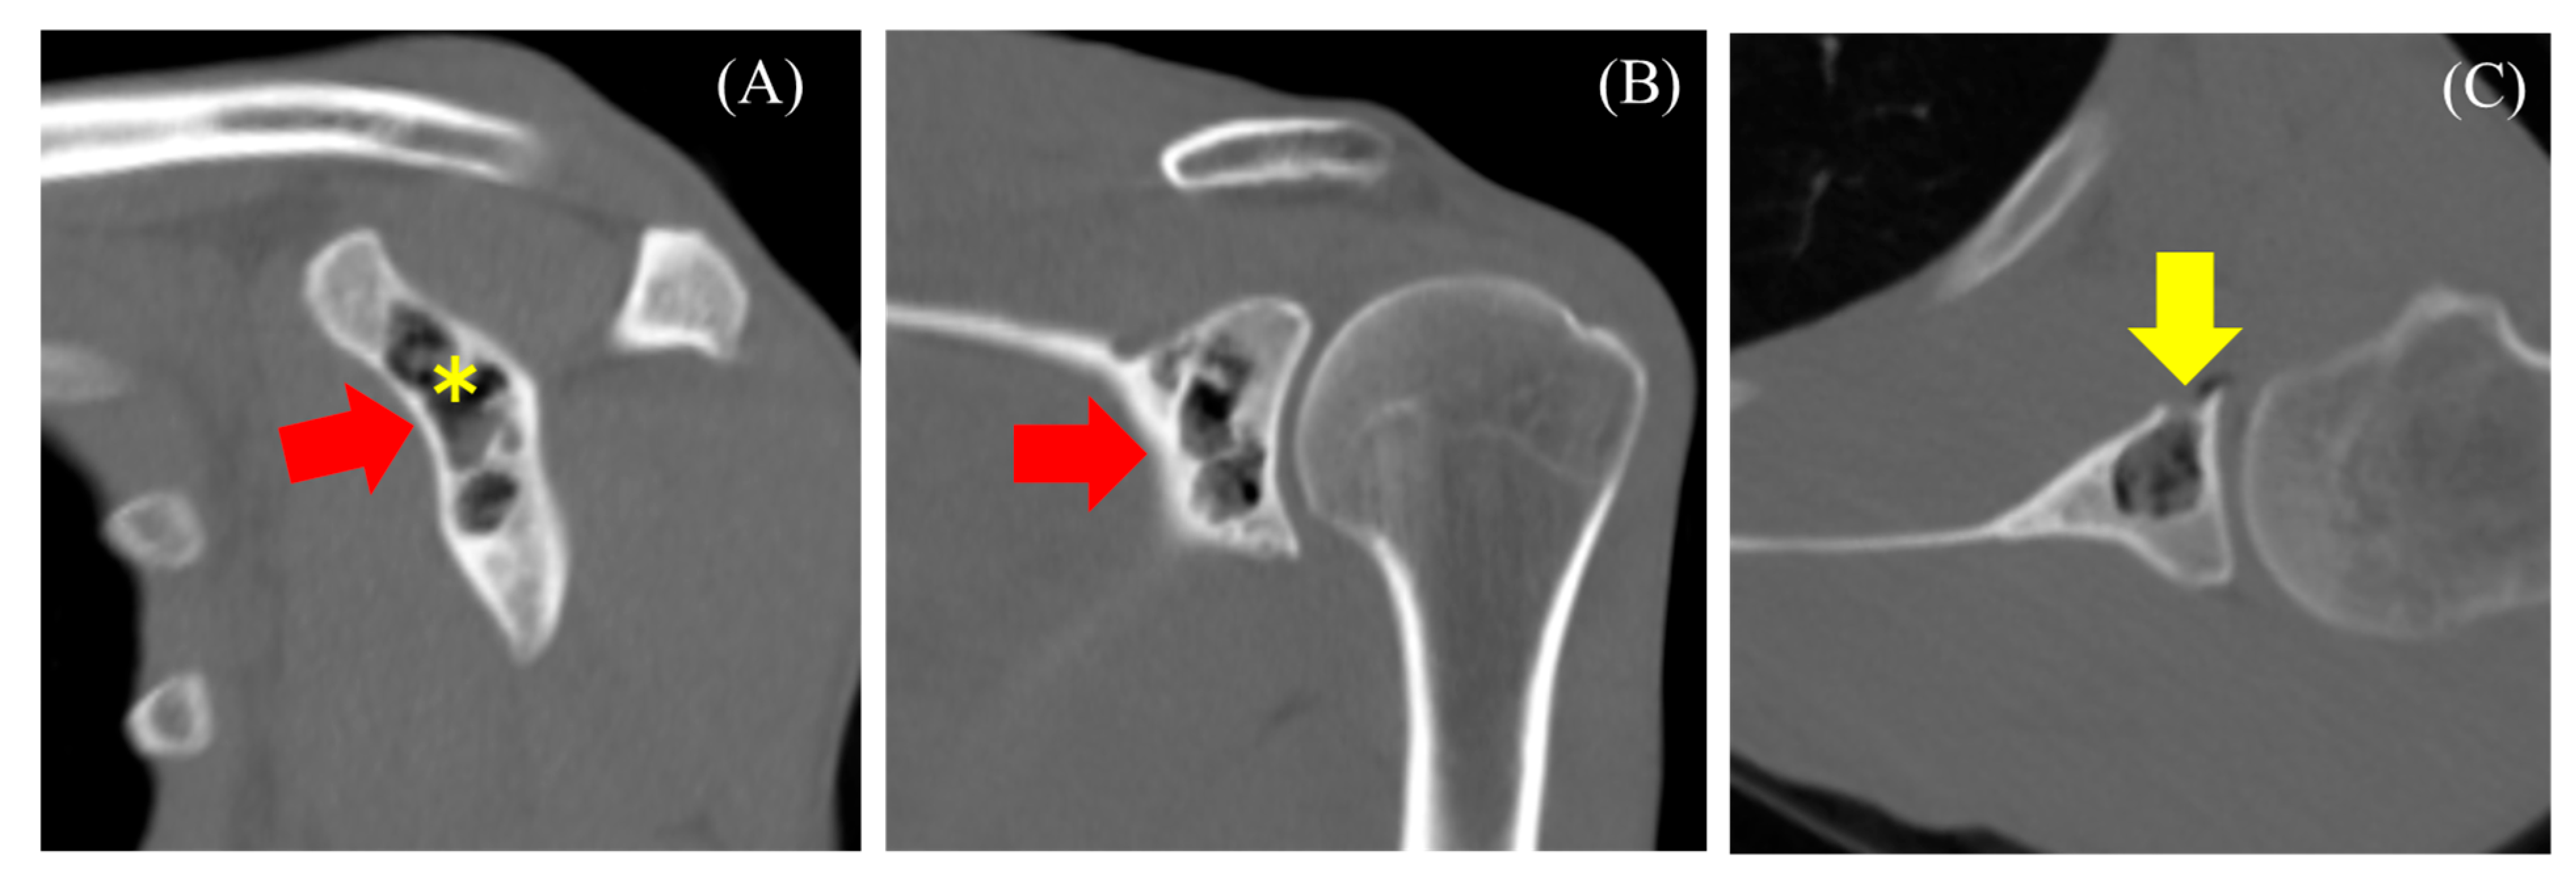

2.1. Case 1

2.2. Case 2